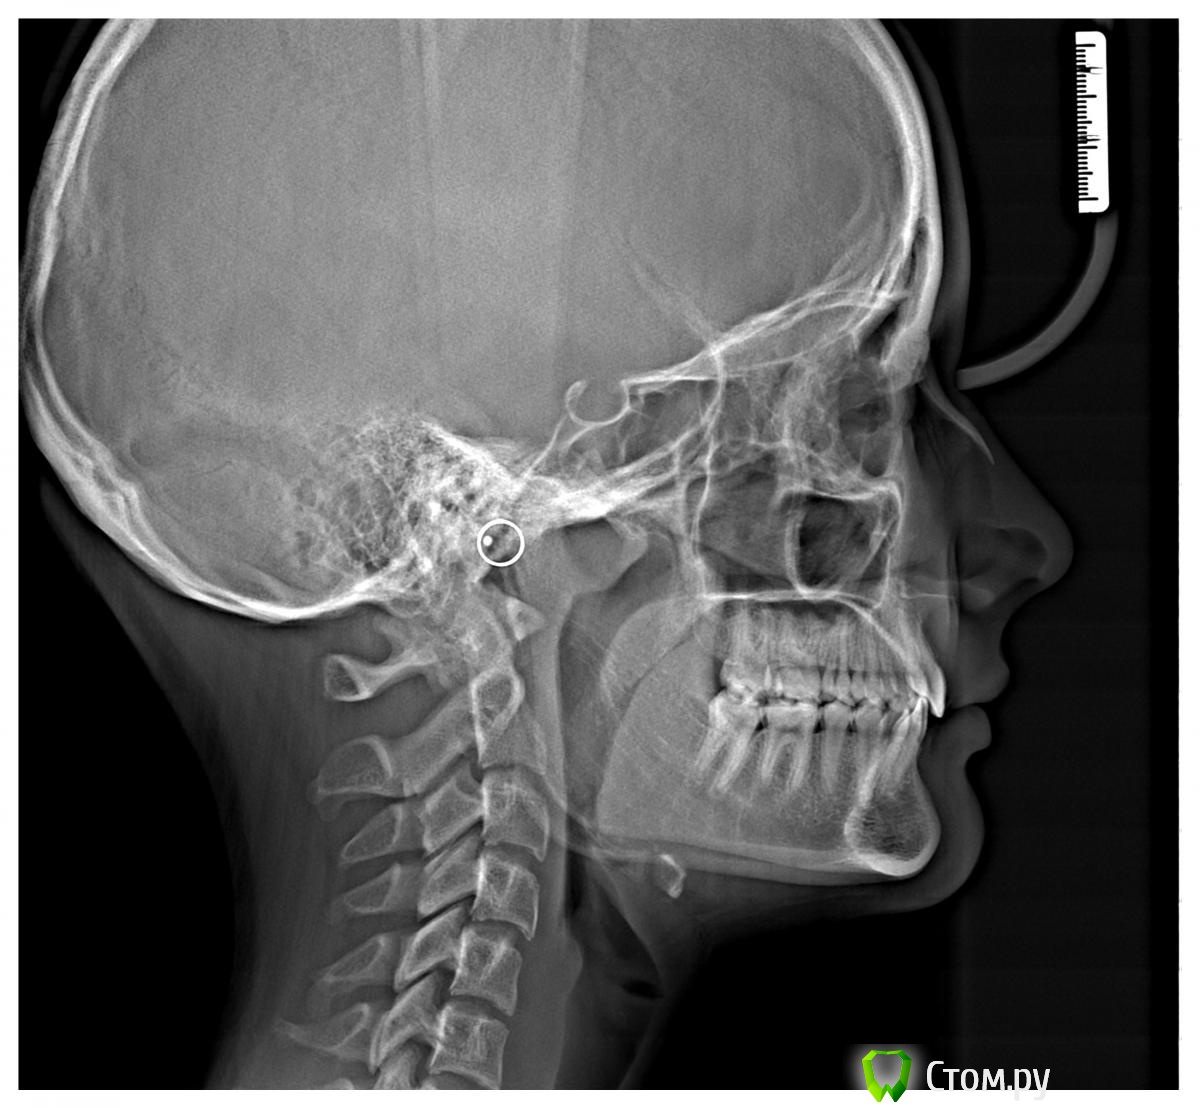

Skip Опубликовано 24 сентября, 2014 Поделиться Опубликовано 24 сентября, 2014 Зачем? Примерный срок имплантации - 18 лет, не рантше. Раздвинуть зубы обратно и потом три года пытаться удержать? Нелогично. По плану лечения согласен с А.О. Но года через 3-4. Пару лет, примерно, уйдёт на создание вертикального измерения окклюзии, плюс RHG по всей видимости. Разумеется, что я это на себя примеряю и с функциональной ортопедией челюстей. Учитывая, что школьница, использование аппаратов только дома, а значит сроки лечения растянутся и не успеешь оглянуться, как 18 лет, тем более они все ранние сейчас)) Беспокойство вызывает вот эта картина на ТРГ, где можно заметить прекрасное соотношение челюстей между собой, но вместе с этим нижняя челюсть дистализирована, а это значит, что существует потенциальный риск развития ДВНЧС, плюс вертикальное измерение опять же: http://i6.pixs.ru/storage/6/7/5/99955jpg_4352041_13969675.jpg Ссылка на комментарий

Джоконда Опубликовано 24 сентября, 2014 Автор Поделиться Опубликовано 24 сентября, 2014 Пару лет, примерно, уйдёт на создание вертикального измерения окклюзии, плюс RHG по всей видимости. Разумеется, что я это на себя примеряю и с функциональной ортопедией челюстей. Учитывая, что школьница, использование аппаратов только дома, а значит сроки лечения растянутся и не успеешь оглянуться, как 18 лет, тем более они все ранние сейчас)) Беспокойство вызывает вот эта картина на ТРГ, где можно заметить прекрасное соотношение челюстей между собой, но вместе с этим нижняя челюсть дистализирована, а это значит, что существует потенциальный риск развития ДВНЧС, плюс вертикальное измерение опять же: http://i6.pixs.ru/storage/6/7/5/99955jpg_4352041_13969675.jpgБлагодарю, Алексей Олегович! Ссылка на комментарий